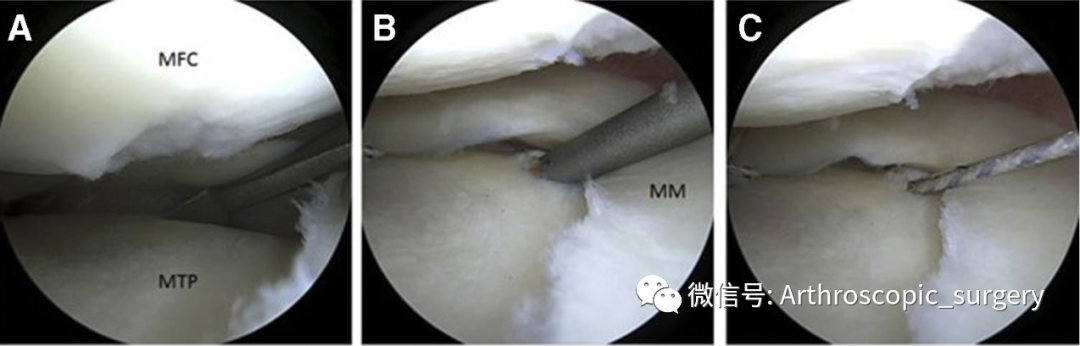

A.缝线通过缝合器在内侧半月板下表面引出,并通过前外侧入口取线;B.通过前外侧入路取出缝线进行打结;C.推结收紧固定;D.最终缝合后的状态